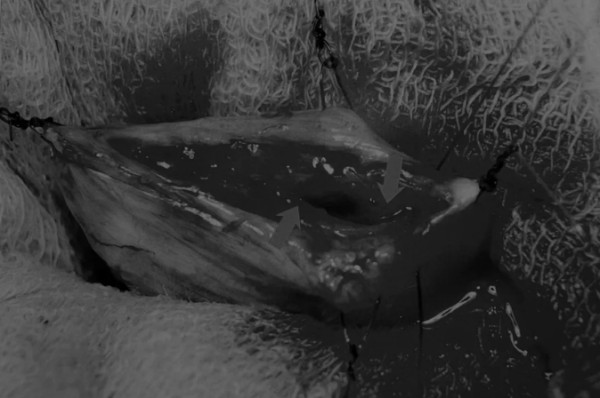

膀胱创面采用单丝合成可吸收缝线缝合,采用外科医生习惯的缝合方式,但注意不要刺穿黏膜层(图6、图7)。

图6 使用简单的连续缝合。尽量不要用针刺穿黏膜层(箭头),以免缝线与尿液接触

图7 缝线应带入足够的切口两侧的膀胱组织,以确保在膀胱充盈时,没有伤口裂开